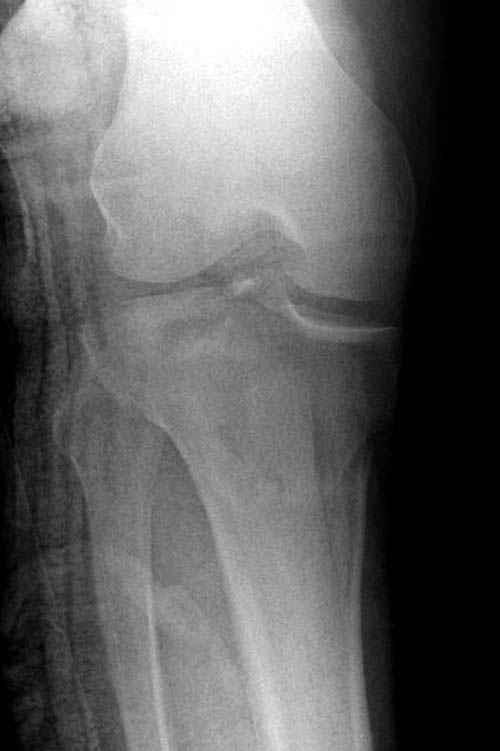

Трудно поверить, что разрекламированная Ортопедическая школа Восточной Украины позволяет такие странные снимки? На прямом снимке сохранен общий контур плато, но не известна судьба импрессии суставной поверхности. На полубоковой?, оставлен без репозиции задне-медиальный отдел, и навряд ли после такой фиксации можно удовлетвориться результатом.

На представленных предоперационных срезах КТ огромный задне-медиальный фрагмент расположен больше кзади, чем медиально. Для планирования, кроме поперечных срезов, надо ориентироваться на корональные срезы, которые укажут топографию верхушки медиального фрагмента.

Представленные снимки не информативны, нужны отдельные качественные снимки коленного сустава и голени без ротации.